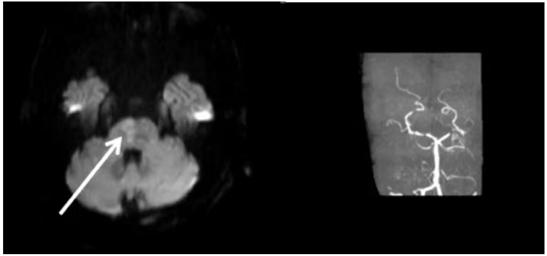

图10 桥脑、双侧小脑半球多发急性脑梗死灶,结合患者房颤病史,考虑为心源性栓子堵塞基底动脉的终末端,引起双侧大脑后动脉和小脑上动脉梗死的基底动脉尖综合征(图源 作者提供)三、穿支动脉病变——粥样硬化/小动脉纤维玻璃样变导致的穿支动脉区孤立梗死灶

二、心源性

急性多发梗死灶,双侧前循环/前后循环;有心源性卒中证据;无相应颅内外大动脉粥样硬化证据;无其他病因(血管炎、凝血异常、肿瘤栓塞等);如排除主动脉弓粥样硬化,为肯定的心源性,如不能排除,为可能的心源性。